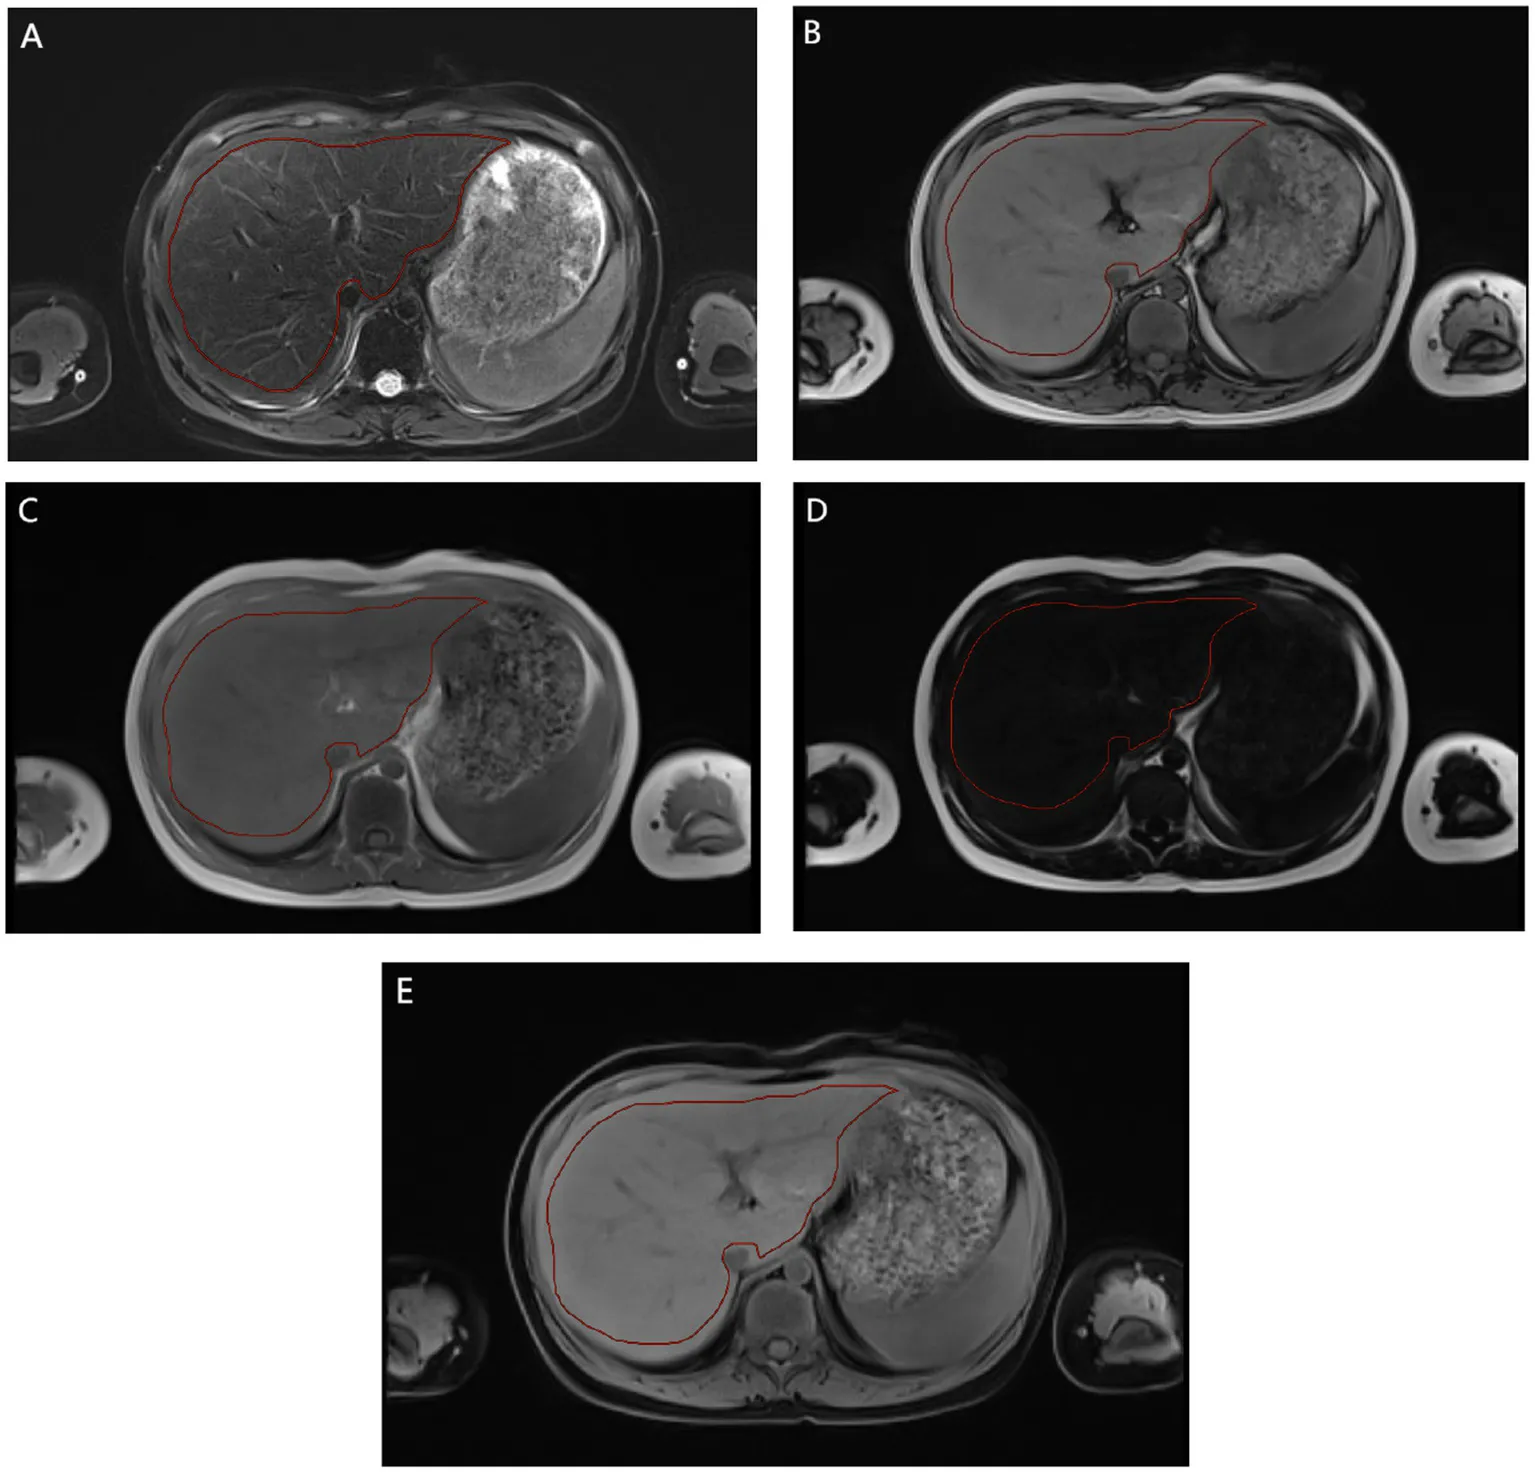

Radiomics feature extraction followed the guidelines of the Imaging Biomarker Standardization Initiative (IBSI) to ensure repeatability and standardization (15, 16). This includes standardized image preprocessing, extracting features from the delineated volume of interest, and applying the IBSI nomenclature to all reported features. Specifically: 1. Image preprocessing: All images are resampled to isotropic 1 × 1 × 1 mm3 voxels using B-spline interpolation. 2. Feature extraction: A total of 1,125 features were extracted from each delineated volume of interest. Its mathematical definitions and calculations strictly follow the IBSI reference manual. 3. Nomenclature: All extracted features are reported using the standardized IBSI nomenclature to facilitate cross-study comparisons. Imageomics analysis included the following steps: (1) Region of interest (ROI) two-dimensional segmentation: all parametric images were selected for manual segmentation of the maximum liver cross section (Appendix E1). (2) Feature extraction: shape features, first-order features and texture features. Shape features describe the basic geometric characteristics of the scratched area, including size, shape and surface roughness. First-order features use common and fundamental metrics to describe the distribution of voxel intensities within the delineated region. Texture features include gray level co-occurrence Matrix (GLCM), gray level free length Matrix (GLRLM), gray level size region Matrix (GLSZM), adjacent gray level color difference Matrix (NGTDM) and gray level dependence Matrix (GLDM). These features are able to capture the spatial interdependence of voxels in an image and show the spatial heterogeneity features of the image, such as gray level variation, spacer size, and roughness. In addition, six filters including exponential, square, square root, log, log-sigma-3-0-MM-3D and wavelet were used to further process the first-order features and texture features. The wavelet filter extracts features from eight wavelet decomposed images. A total of 1,125 features were extracted. (3) Radiomics feature selection and model construction: the data from the two medical centers were randomly divided into A training set (medical center A, 187 cases; Medical center B, 65 cases) and validation set (medical center A, 80 cases; Medical center B, 28 cases). All radiomic features were normalized using minimum–maximum values to eliminate the magnitudes of different features by scaling values to [0, 1]. The sample variance F value (f_classif) was used to screen out 20 important features for classification. In this study, two methods were used to select significant radiomics features for the training cohort from feature subsets of different parametric MRI sequences, alone or in combination. These methods include least absolute shrinkage and selection operator (LASSO) and Logistic Regression (LR). LASSO selected the relevant features according to the best parameter (alpha). LR was used to select the optimal features. In the construction of the LR model in this study: K = 5 in k-fold cross validation. The evaluation index was roc_auc. The elasticnet is selected as the penalty parameters, with the penalty coefficient C = 1 and the l1_ratio = 0.5. And the maximum number of retained features. On this basis, machine learning models are built based on the selected features and logistic regression. The Rad score constructed for each patient by the logistic regression classifier will help predict the prognosis of liver iron burden in TM patients after HSCT.

Appendix E1

Region of interest (ROI) two-dimensional segmentation: all parametric images were selected for manual segmentation of the maximum liver cross section.